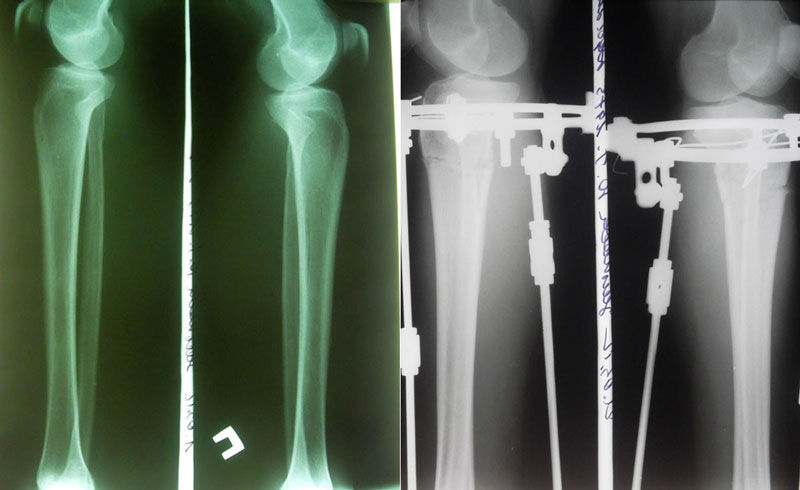

Я приехала 1 марта, сдала анализы, 2 марта ноги мои сломали) На следующий день Малиновка и Жасмин притащили ходунки и Жасмин так спокойно сказала-вставай...У меня аж все похолодело от страха, но встала..Все-таки нашатырь-классная вещь!!)))Постояла несколько секунд-и в койку...Трясло от слабости..Больновато, конечно, было, но терпимо,может уколы еще влияли..На след день сделала пару шагов сама, потом дошла до раковины..Ну, а когда поджало (имею в виду жуткое желание побыть в туалете одной